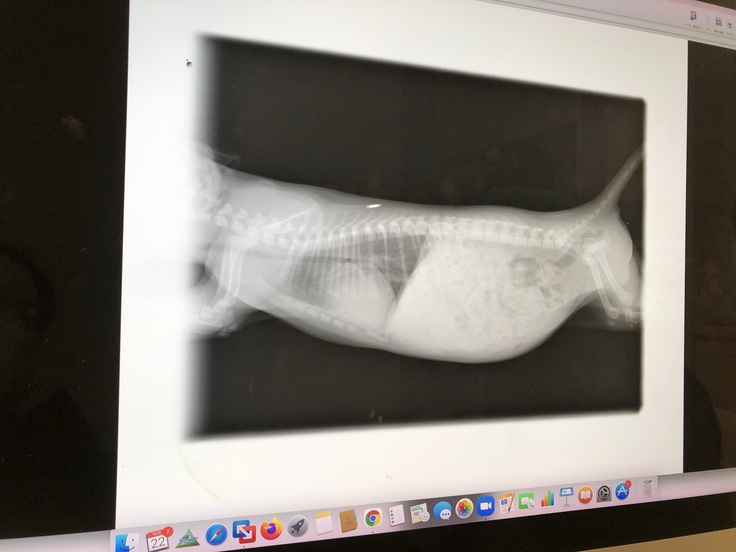

その時点ではどんな病気なのかも分からず、引き取ってすぐに病院で検査をして頂いたところ「動脈管開存症」と判明。

諸々の検査だけでも5万円。更に手術の見積もりが42万円。

この病気は早くに手術をすれば長く生きる可能性が高いそうです。

手術は11月3日に無事終えました。

443,784円